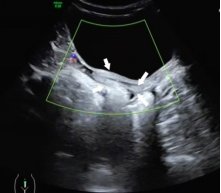

未发育的子宫

(白色箭头所指)

发育的子宫